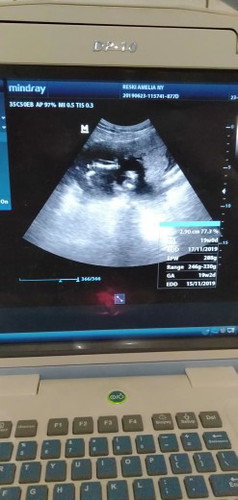

Bun... Mau tanya! Dalam buku pink usia kandunganku 18weeknd2day Tapi pas usg bidannya blg usia kandunganku 19weeknd3day Maaf bun soalnya sy binggung Berat badan kandunganku normal tdk bunn???